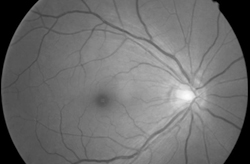

• ¾ÈÀúÃÔ¿µ

¸Á¸· Á߽ɺÎ(½Ã½Å°æ, Ȳ¹Ý)¸¦ ÃÔ¿µÇÏ¿© ³ì³»Àå,¸Á¸·ÁúȯÀ» Á¡°ËÇÕ´Ï´Ù.

• ½Ã½Å°æ¼¶À¯ÃþÃÔ¿µ

½Ã½Å°æ¼¶À¯Ãþ°á¼ÕÀ¸·Î ½Ã½Å°æ ¼Õ»óÀ¯¹«°Ë»ç¸¦ ÆÇ´ÜÇÏ¿© ³ì³»ÀåÀ» Áø´ÜÇÒ¼ö ÀÖ½À´Ï´Ù.

• ¾È±¸±¤ÇдÜÃþÃÔ¿µ

·¹ÀÌÀú¸¦ ÀÌ¿ëÇÏ¿© ¸Á¸·¹× ½Ã½Å°æÀ» ´ÜÃþÃÔ¿µÇÏ¿© ¸Á¸· ¹× ½Ã½Å°æ ÀÌ»ó, ³ì³»ÀåÀ» °Ë»çÇÕ´Ï´Ù.